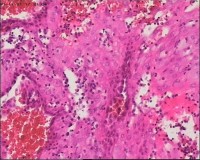

性别

女

年龄

20岁

停经3月,阴道不规则流血7天。

宫刮物

灰白灰红碎组织一堆,大小为7*6*1cm,部分组织呈水泡状

水肿的绒毛和蜕膜,没看到增生的滋养细胞。必要时可做IHC除外部分葡萄胎,并结合临床HCG。

雾蒙蒙:

需要除外一下部分性水泡状胎块可能

考虑葡萄胎